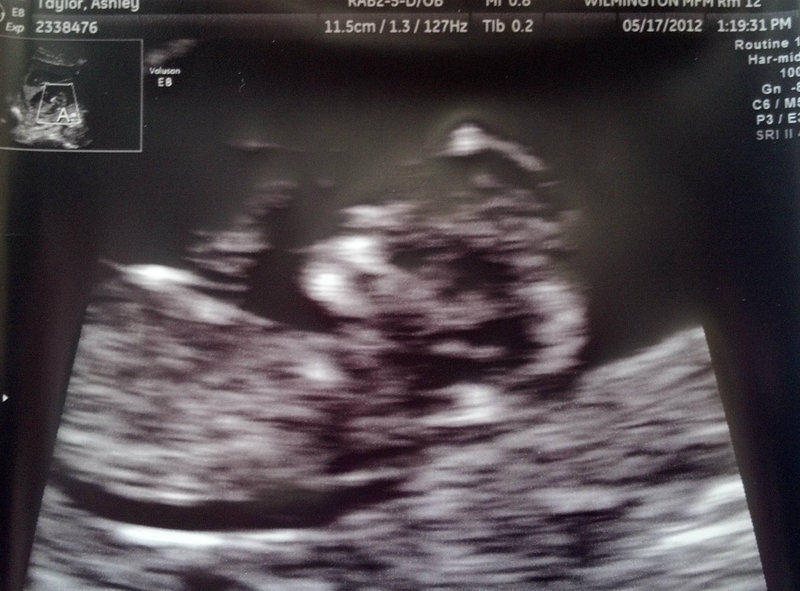

Attachment 3160

Hmm, not sure about the shadown on top of the nub for B. I am guessing both boys.